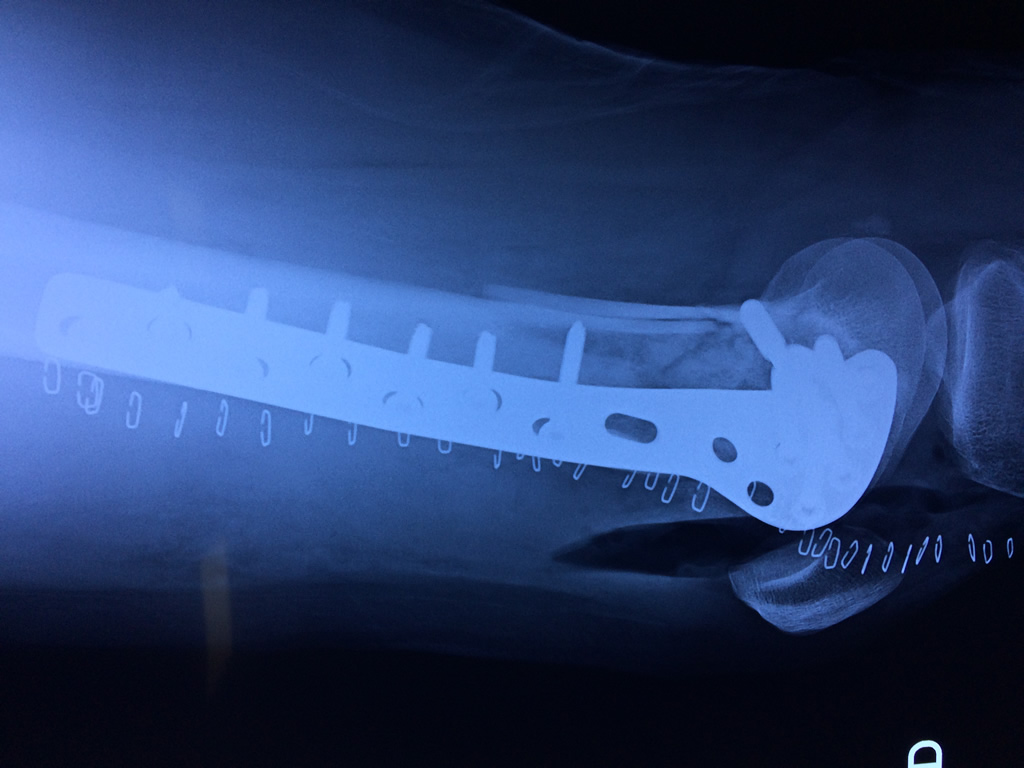

Cirugías de Muñecas